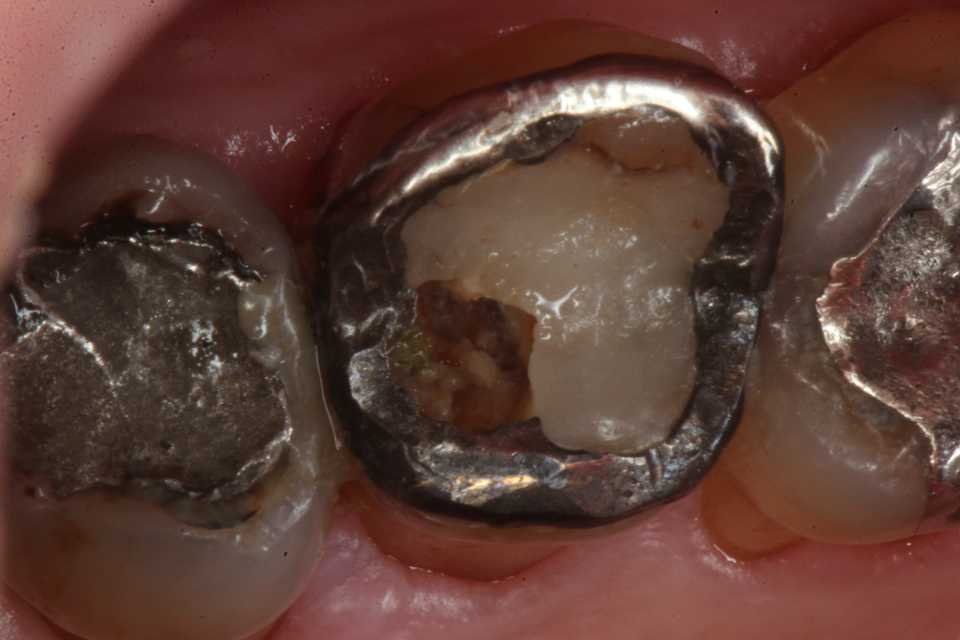

50代女性、左上5-7ブリッジ脱離、7番2次カリエス+Per(根尖性歯周炎)、強度の外傷性咬合この方、ひどい食いしばりで歯が壊れてしまう。噛み合わせの左下7番も歯冠が崩壊しつつある。7番はブリッジが脱離していて、内部は虫歯でドロドロ。Perつまり根管充填が緊密ではなく、歯根内部は細菌だらけで根の周りにはひどい炎症がある。まずはレントゲン写真から。7番の歯根の周りが炎症で黒くなっているのが分かると思う。ブリッジを全部外すと咬合が狂うので、とりあえず7番だけカットして内部を見てみた。根管充填材が見えるところまで軟化象牙質を除去して、3MIX+α-TCPを入れて根管内部を殺菌することにした。根管充填材の周りは黒くなっているのが見えると思うが、これは硫酸塩還元細菌の代謝産物の硫化鉄:FeSで、理想に反して根管充填材はゆるゆるの緊密充填ではないことを示している。このような状況は普通のことだ。歯根内部は細菌だらけということだが、ゆるゆるだから根管充填材を全部除去する必要もない。ゆるゆるの隙間から3MIX(抗菌剤)は浸透し根管は殺菌される。外傷力を弱めるために咬合調整を繰り返している。コア部分は隙間に細菌由来の黒色物質FeSがこびりつき、真っ黒。ポンティック下も細菌のコロニーでドロドロ歯質は残っているように見えるかもしれないが、ボンディング材が効く程度に軟化象牙質(虫歯)を除去すると、残根状態になる。つまり通常治療では抜歯しかないということだ。しかもPerでグラグラの動揺度2〜3、垂直性同様有りだ。とてもこのままではブリッジの支台には使えそうもない。ピンク色の根管充填材が見えると思うが、周りは真っ黒だ。その真っ黒になった隙間から細菌は侵入するし、3MIXも浸透する。こうではない緊密な根管充填治療は垂直加圧法でしか見られない。3MIX+α-TCPCR(ダイレクトボンディング)で覆う。これでないと微小漏洩が起こり失敗する。丸い形はラウンデッド・コアと呼び、この形が咬合力を内向きに集中させ歯根を守る。ポストは歯根の外側にこじるような応力を生じるので歯根を壊してしまいやすい。補綴物が必要な時はピンレッジで維持力を得る。これはCAD/CAMでは作れないだろう。これで2〜3週間様子をみる。外傷性咬合のコントロール(ナイトガードや行動療法)をしながら。つづく